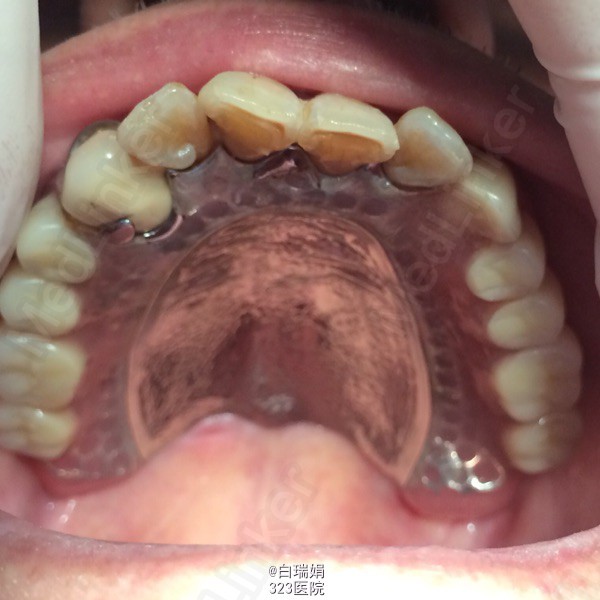

诊断:1、牙列缺损 2、左上烤瓷冠桥松动 3、左上3、4慢性根尖周炎 处理:1、拆除左上烤瓷冠桥,拔除左上5、7 2、左上3、4截冠后常规行根管治疗 3、左上3治疗后无症状制作根面磁性附着体 4、粘接根面附着体后取上下颌模型,纪录咬合关系,制作活动义齿 5、试戴蜡型,调整咬合关系,戴活动义齿,调合抛光,粘接另一半磁铁